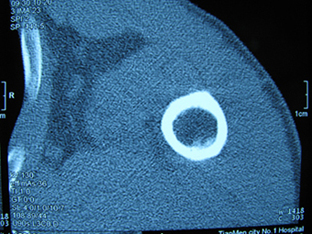

标题: X6404B:肱骨骨质破坏(CT片) [打印本页]

标题: X6404B:肱骨骨质破坏(CT片)

男,50岁,左肩部轻微疼痛,活动不便5个月就诊,近十天加重,无红肿热,间断理疗治疗无好转,既往5个月前左肩轻微拉伤史

骨巨?动脉瘤样骨囊肿?

内生软骨瘤。

内生软骨瘤。

内生软骨瘤?-----------

年纪大了,先要排除转移瘤。

髓腔内软组织肿块并斑片状钙化,考虑高分化软骨肉瘤可能性大。

考虑骨巨或动脉瘤样骨囊肿。

内生软骨瘤可能性大,期待结果。

孤立性骨囊肿。

内生软骨瘤可能性大

其内可见钙化,考虑软骨源性肿瘤,内生软骨瘤可能

但由于年龄较大,恶性软骨肉瘤待排

肱骨头内巨大软组织肿块并斑片状钙化,内生软骨瘤?骨巨细胞瘤?软骨粘液样纤维瘤?期待结果!

髓腔内软组织肿块并斑片状钙化,考虑高分化软骨肉瘤可能性大。

内生软骨瘤可能性大

肱骨头内巨大软组织肿块并斑片状钙化,内生软骨瘤?骨巨细胞瘤?软骨粘液样纤维瘤?期待结果

考虑内生软骨瘤?骨巨细胞瘤?

内生软骨瘤?骨巨细胞瘤?

先要排除转移瘤。